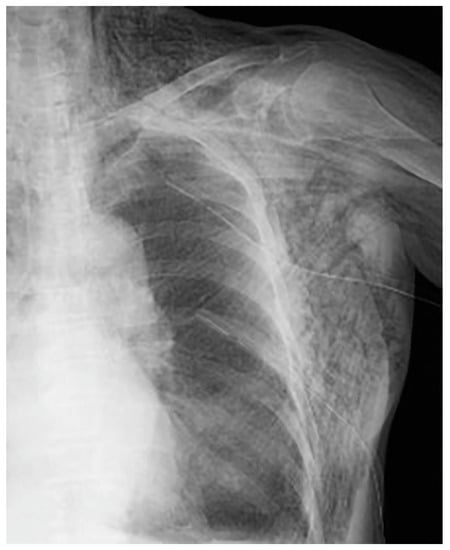

The following day, the subcutaneous emphysema showed a trend of enlargement on the chest X-ray image. Therefore, an additional drain (20 Fr) was placed from the left anterior thoracic region into the left thoracic cavity (Figure 4).

Figure 4.

An additional drain (20 Fr) was placed from the left anterior chest to the left thoracic cavity.